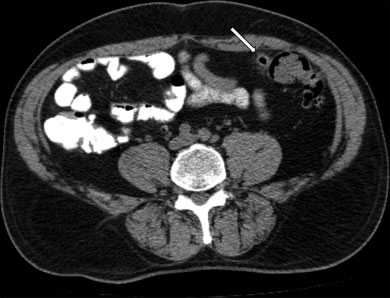

Estadio IIA: Absceso > 4 cm (sin aire libre distante). Se recomienda drenaje percutáneo guiado por imágenes (►Figs. 5 y 6).